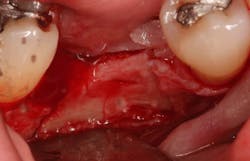

A crestal incision was made on the edentulous ridge and sulcular incisions were made on adjacent teeth. A partial-thickness flap was elevated on the facial to maintain a periosteal blood supply to the buccal plate. The periosteum was left on the buccal plate to provide additional blood supply by using a sharp dissection (whereas a blunt elevation [full-thickness flap] would have involved elevation of the periosteum off of the bone with the flap).

A Piezosurgery device with saw inserts was used to create strategic cuts at site No. 30 down the center of the ridge to a depth of 10 mm. Piezosurgery uses ultrasonic vibrations to remove bone, much like a high-speed handpiece but causing less inflammation. Oblique cuts in the buccal bone were made diverging apically to make the base of the isolated portion of the buccal plate wider than the coronal portion to allow for maximum blood supply. A shallow cut was made in the apical portion of the bone, connecting the vertical cuts to allow for the newly isolated trapezoidal piece of buccal plate off which to hinge. A mallet and chisels were used with gentle tapping to out-fracture the buccal bone and to create space in the middle of the ridge. Careful attention was made to ensure that the apical portion of the split ridge was kept intact to allow for blood flow to the isolated portion of bone.

An osteotomy was then created, extending to the apical portion of the split ridge in preparation for implant placement. A bone-level tapered 4.1- x 12-mm implant was placed with a flat cover screw. A mixture of cancellous and cortical allograft particulate was infused with autogenous PRGF and packed around the implant on the mesial and distal aspects. The newly out-fractured buccal plate was positioned intimately adjacent to the buccal portion of the implant, and additional graft material was placed over the buccal plate to further augment the bone horizontally and reduce the risk of buccal-plate resorption during healing. A 25- x 30-mm Ossix Plus membrane was soaked in saline for three minutes and trimmed to extend 3–4 mm beyond the confines of the bone graft and roughly 1 mm from the adjacent teeth.